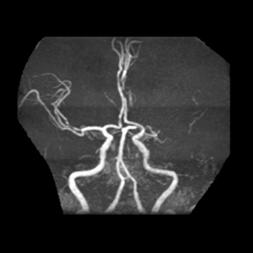

十九、锁骨下动脉盗血综合征合并开窗畸形

例37:左锁骨下动脉起始段闭塞、左侧锁骨下动脉盗血综合征合并基底动脉近段开窗畸形

病例38:烟雾病合并右侧大脑前动脉A2段开窗畸形